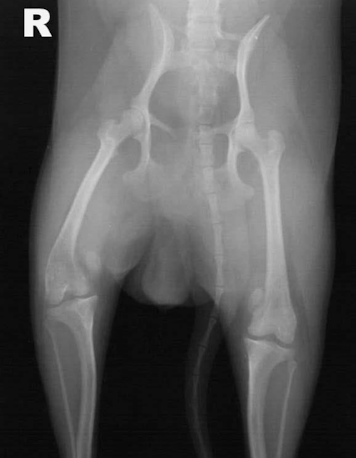

Who and where do we often see DJD?

Medium/large breed dogs

hip, shoulder and stifle

Four common locations for DJD/OA

shoulders

hips

stifle

elbow

Hip DJD

acetabular rim osteophytes

femoral head osteophytes

morgan line (poor example)

subchondral sclerosis of acetabular rim